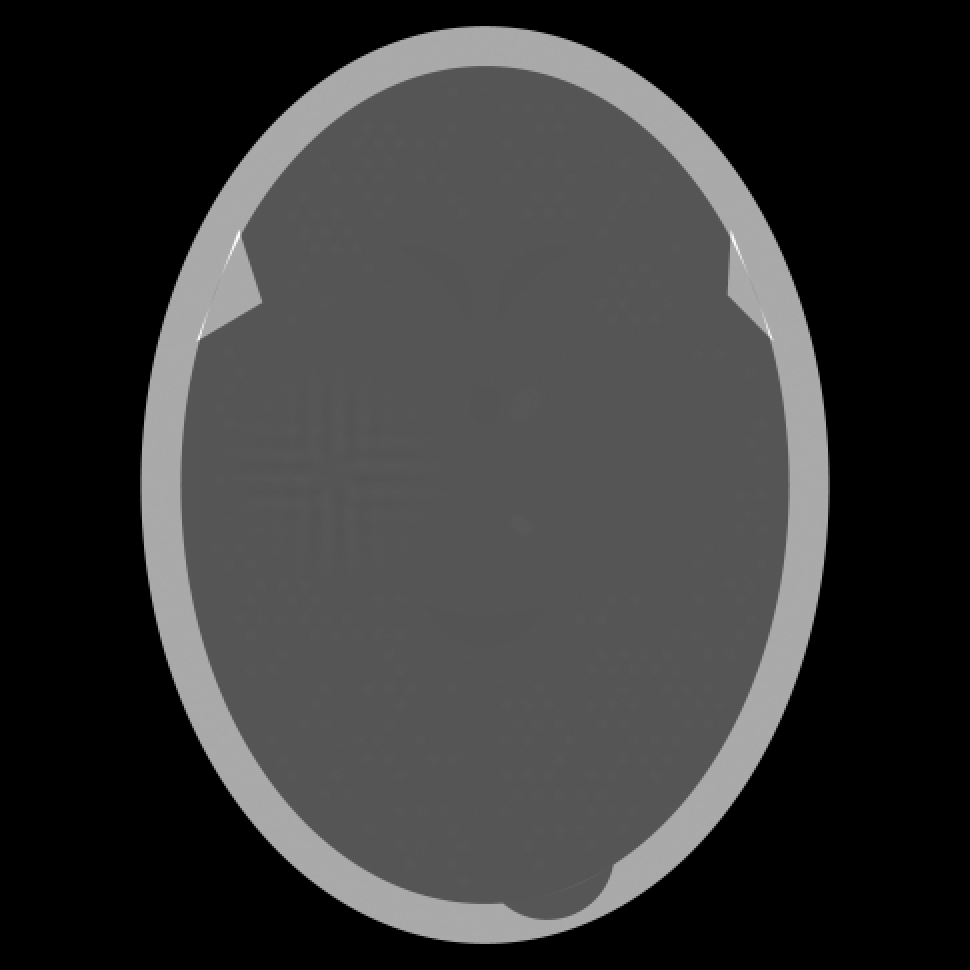

Figure 3: Reconstructions from 360 projections by (a) filtered back-projection, (b) the algorithm ART, (c) TV-Based Superiorized Version of ART, and (d) Shearlet-Based Superiorized Version of ART.

For this anecdotal experiment we use three different numbers of views (i.e., projections): 180, 360, and 720. We emphasize that, in the currently-described anecdotal experiment, there is only one phantom (which provides the ground truth); random generation of local inhomogeneities and of tumor locations is done only once and the same arrangement of local inhomogeneities and of tumor locations is used when generating the projection data for the three different numbers of views.

We present the visual results of the reconstructions produced by these algorithms when using 180, 360, and 720 projections in Figures 2, 3, and 4, respectively. We now give our impressions based on these visual results.

As expected, the greater are the number of projections, the better are the reconstructions produced by any of the four algorithms. However, even with 720 projections, the reconstruction produced by the Shearlet-Based Superiorized Version of ART still shows some high-frequency artifacts and the small tumors are less visible than in the images produced by the other three algorithms.